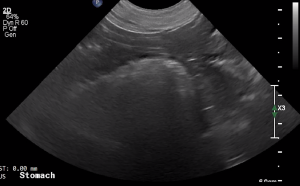

SIMON Ultrasound Database

This ultrasound database is a free resource for students and doctors!

Our collection includes videos of dogs, cats, horses, cows, humans, and many other species!